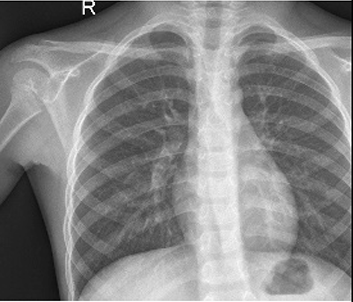

Table 6 Fused image output.

From: Multimodal medical image fusion combining saliency perception and generative adversarial network

Alternate image